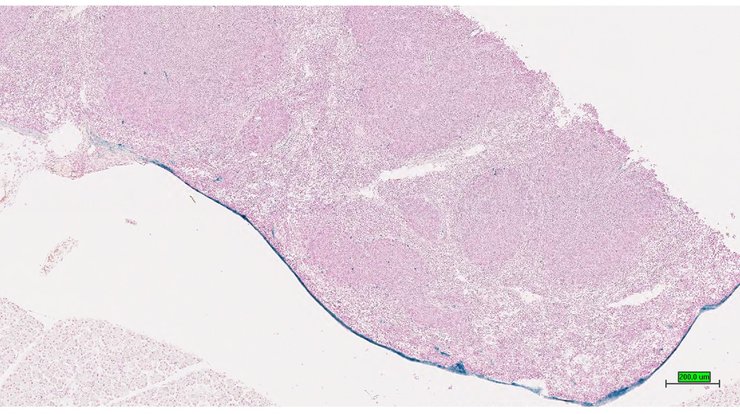

TS28: spleen Present UC Davis_1878593

Specimen UC Davis_1878594: postnatal adult; Apbb2tm1.1(KOMP)Vlcg/Apbb2+ (more )

Structure Level Pattern Image Note

TS28: spleen Present UC Davis_1878594

TS28: spleen Present UC Davis_1878637

Specimen UC Davis_1878638: postnatal adult; Apbb2tm1.1(KOMP)Vlcg/Apbb2+ (more )

TS28: spleen Present UC Davis_1878638